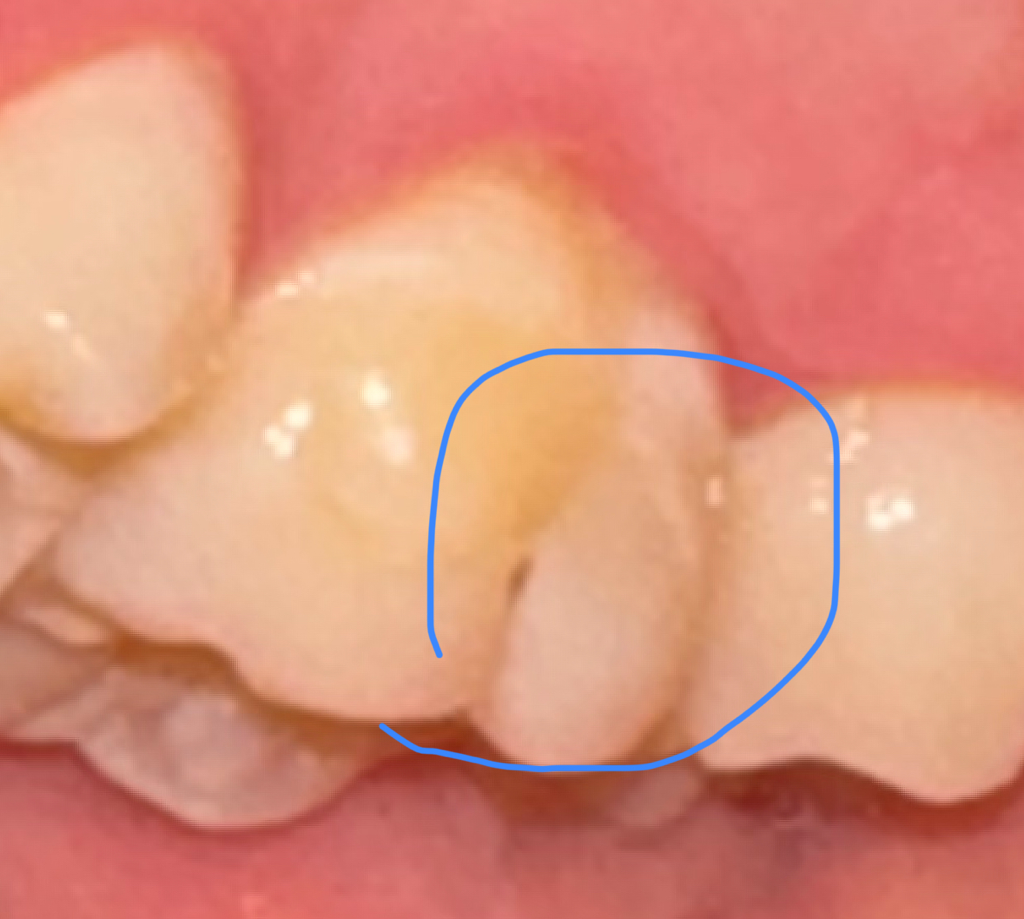

사진속 치아 겉면에 충치가 있어요

사진 속 치아에 작은 충치가 있어요현재 치과 갈 시간을 내기 많이 어려운 상황이에요

통증은 한 달 전에 저부분이 하루동안 아주 약간 찌릿하길 래 휴대폰으로 사진을 찍으니 충치가 있다는 걸 알게되었고 요 통증이 심한게 아니라 제가 예민해서 잘 느낀 거예요

사진을 보면 다른 치아는 다 노란빛이 도는데 동그라미 친 부분만 하얀듯한 느낌이 드는데요

충치때문에 속이 썩어서 그런 걸까요?

고통은 아주 잠깐 있다가 사라져서 하나도 안 아픈데 알고 보면 법랑질이 아니라 상아질까지 잔뜩 썩어있을까봐 걱정

돼요ㅠㅠ

충치로 인해 검은색이 된 치아 표면적이 굉장히 작던데 양 치를 열심히해도 안에서 썩어들어갈까요...?